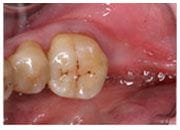

治療前

治療後